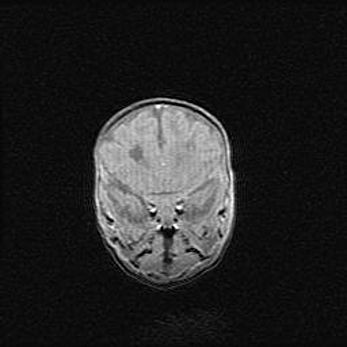

Открытая гидроцефалия.

Возраст: 9 месяцев 12 дней

Вес: 6800 г

Пол: мужской

Окружность головы: 41,5 см

Срок гестации: 28 недель

Гидроцефалия головного мозга у новорожденных имеет характерный признак: опережающий рост окружности головы приводит к визуально хорошо определяемой гидроцефальной форме сильно увеличенного в объёме черепа. Детские неврологи определяют следующие симптомы гидроцефалии у грудничков: выбухающий напряжённый родничок, частое запрокидывание головы, смещение глазных яблок к низу.